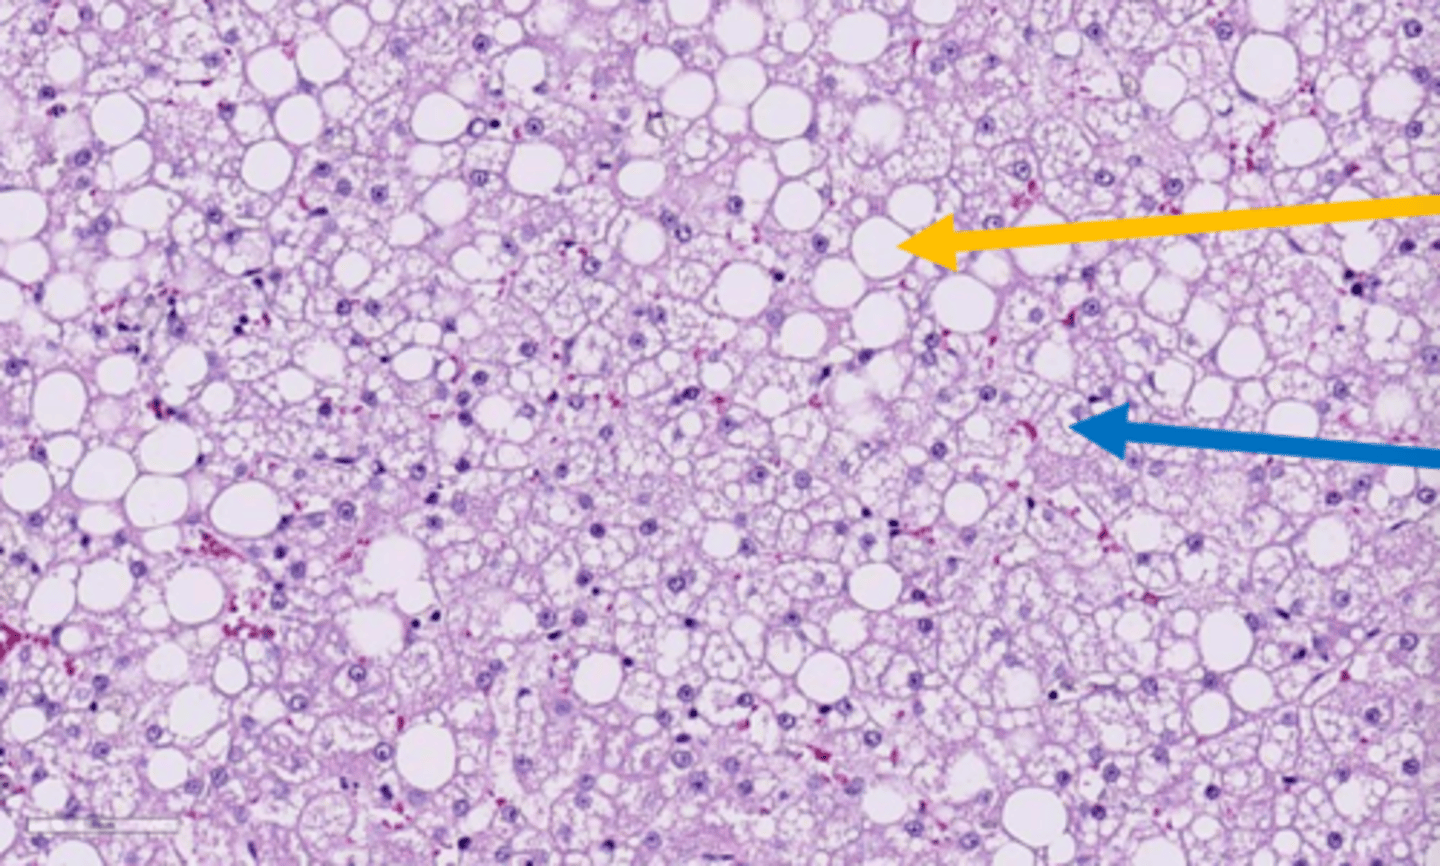

macrovesicular lipidosis

Which type of lipidosis is this describing?

Large, clear, sharply defined vacuoles that are larger than the nucleus, distend the

cytoplasm, and displace the nucleus to the periphery of the cell

macrovesicular hepatic lipidosis

yellow arrow?

microvesicular hepatic lipidosis

blue arrow?

displaced nucleus

blue arrow